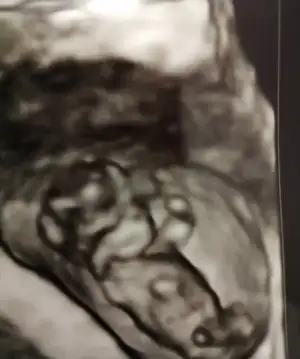

Mrb 13 haftalık cinsiyetine bakarmısınız

Eklentiler

• IMG_20200502_152459.webp

IMG_20200502_152459.webp

30,6 KB · Görüntüleme: 65